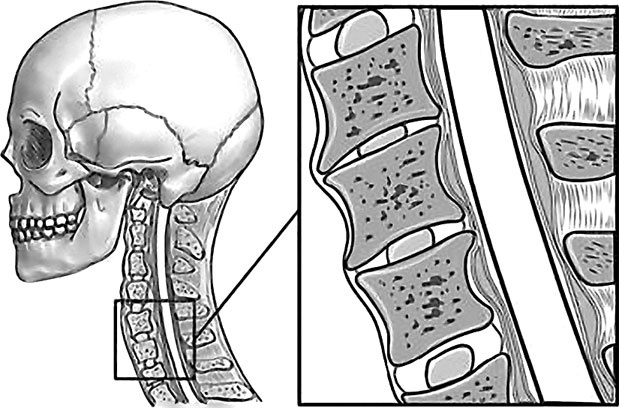

Подобные симптомы могут вызываться спазмами как позвонков, так и мышц шеи. К примеру, перенапряжение затылочных мышц зачастую ведет к головным болям и к проблемам со зрением. Так что шейный отдел позвоночника, состоящий из 7 позвонков, должен иметь и достаточную длину, и определенную статику (рис. 67).

Рис. 67. Нормальная статика шеи. Правильный физиологический изгиб: А=А1

А что в действительности имеем мы? Обычно, даже при здоровом позвоночнике (только где его найдешь?), он начинает с возрастом деформироваться, «проседать», менять статику. Появляется симптом смещенной вперед и запрокинутой назад головы (рис. 68).

Рис. 68. Гиперлордоз шейного отдела позвоночника: B > B1

В результате небольшой физиологический изгиб гипертрофируется, что ведет к проваливанию шейных позвонков вглубь шеи, особенно интенсивно при «сидячей» работе. Формируется гиперлордоз шейного отдела позвоночника.